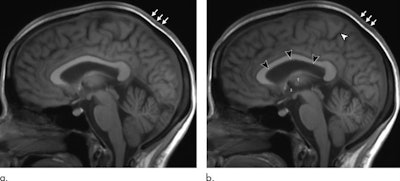

When the researchers compared MR images before time in space and one day after the astronauts' return, they discovered a number of statistically significant changes, including the following:

- Increased mean total volume in the brain of 28 mL (p < 0. 001), most of which was due to white matter of 26 mL (p < 0.001)

- Increased mean enlargement of lateral ventricles of 2.2 mL (p < 0001)

When brain volume and CSF were combined, the statistically significant increases held steady for one year. In addition, six astronauts (55%) showed a significant decrease in the mean pituitary gland of 5.3 mm, compared with 5.9 mm in the preflight MRI (p < 0.01).